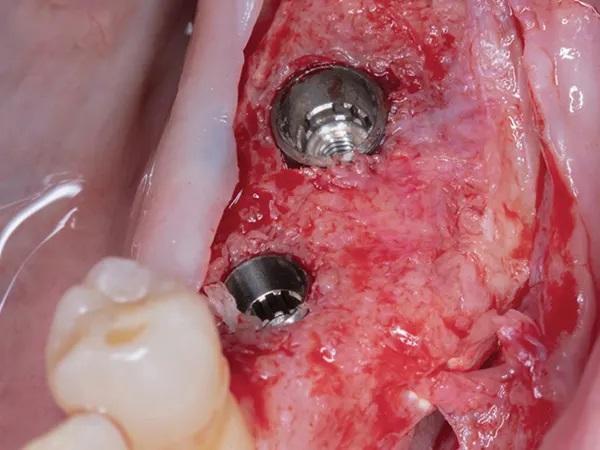

Фото 10: Крепления имплантатов in situ.